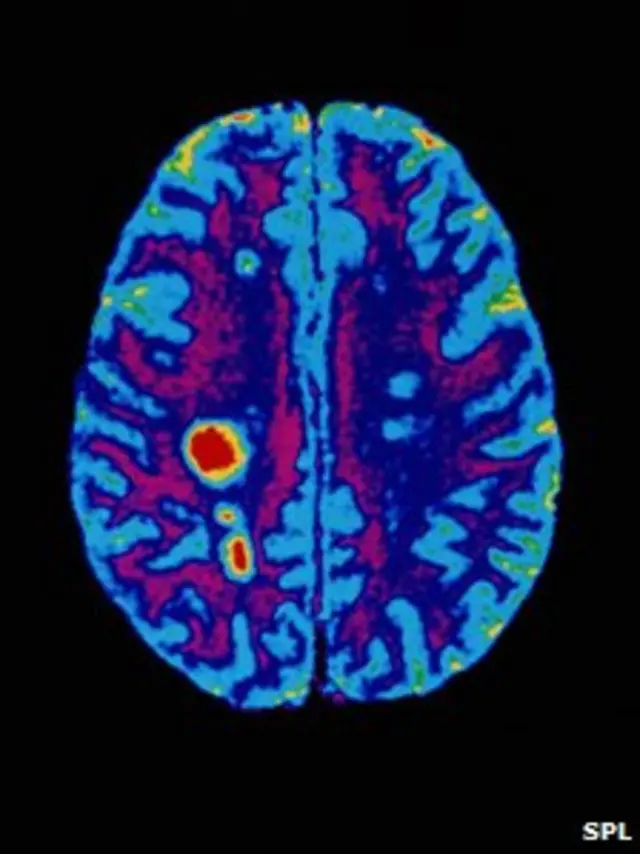

MS hastalarının beyin dokularındaki yapısal değişikliklerle farklı hava düzenleri ve mevsimler karşılaştırıldığında, hastalığın şiddetinin bahar ve yaz aylarında arttığı belirlendi.

Sonuçta bir yılın sonunda toplamda ortalama 22'şer beyin tomografisi uygulanan deneklerden 31'inin beyin dokularında 310 yeni yapısal değişiklik tespit edildi.

Uzmanlar, bu lezyonların ortaya çıkma olasılığının, bahar ve yaz aylarında diğer aylara kıyasla üç kat daha fazla olduğunu söylüyor.